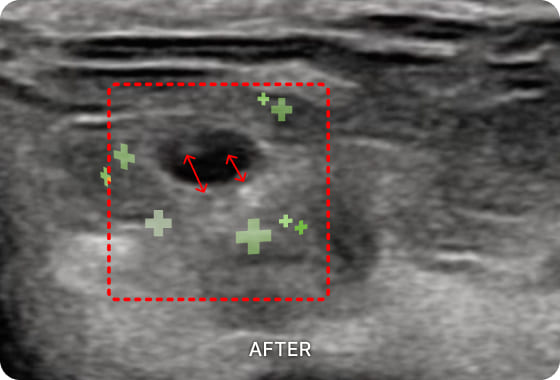

초음파 검사를 통해

수부건초염 통증의 직접적인

원인을 확인할 수 있습니다.

손목에 존재하는 1~6 구획의 건초 상태를

진단하고 정확한 부위를 치료하여 손목과

손가락 통증을 해결합니다.

01. PDRN 약침

PDRN 약침은 인체의 DNA와 90% 이상 유사한 구조로 세포 증식을 활성화하여

손상된 조직을 복구하는 효과가 뛰어납니다. 초음파를 활용하여 신경을 압박하는

염증을 박리하고 손상된 조직을 재생합니다.